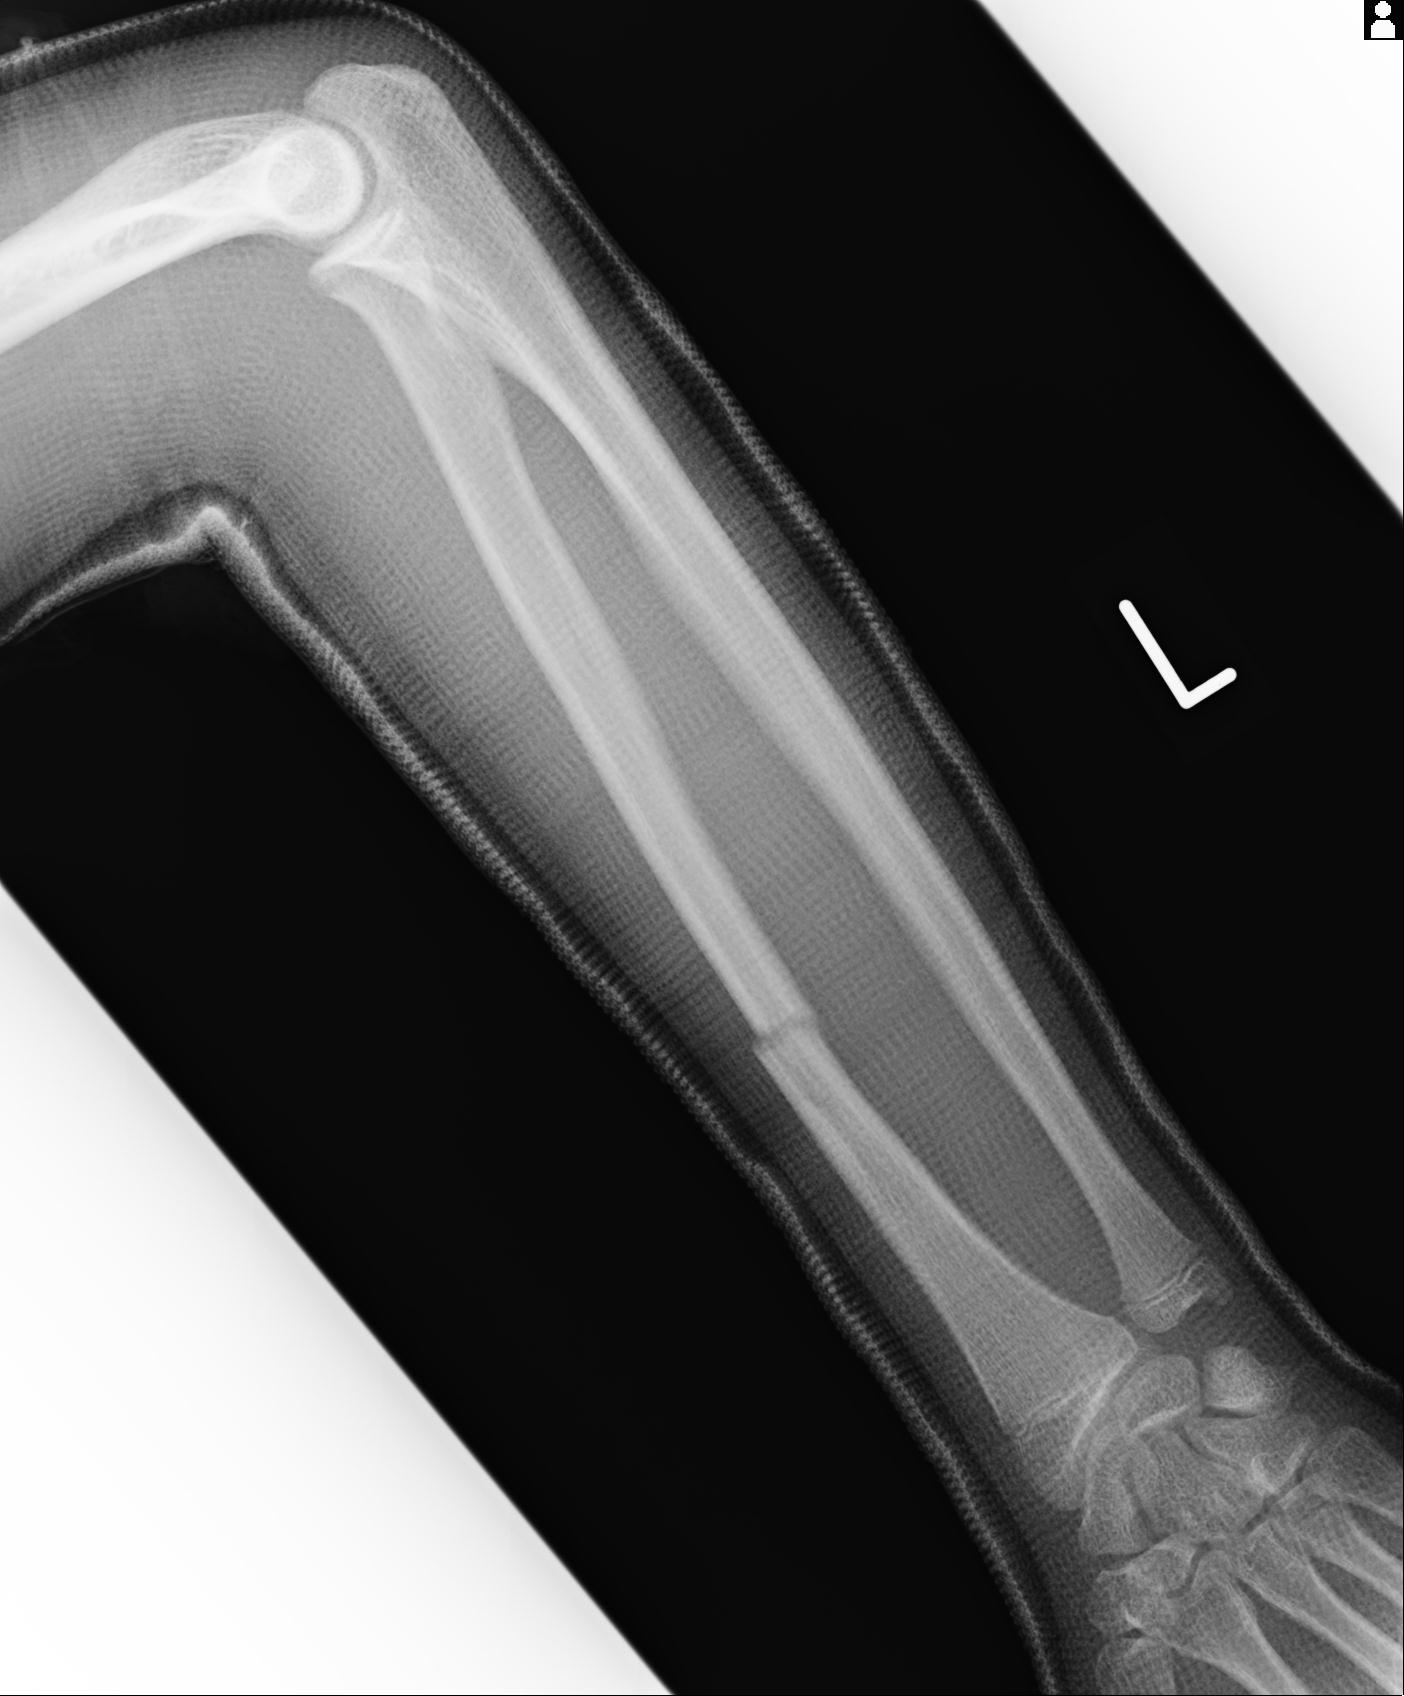

110211 1/6 1/8 左前腕 4R 15歳男性 橈骨骨幹部骨折